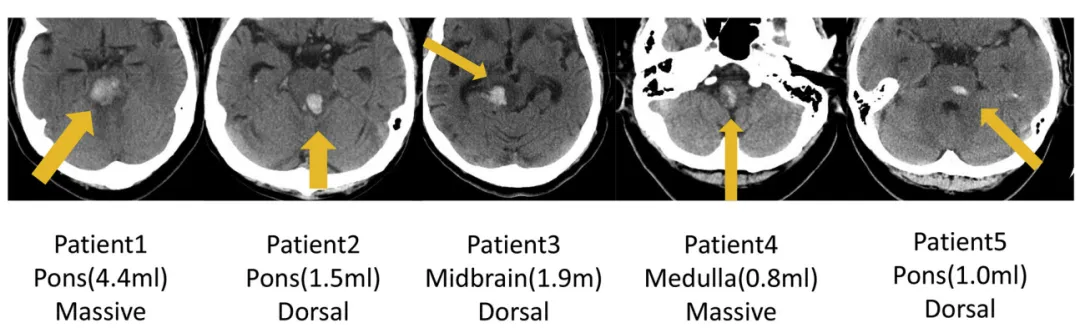

INC巴教授2018年发表论文《Surgical Treatment for Primary Brainstem Hemorrhage to Improve Postoperative Functional Outcomes》中讨论了5例接受手术治疗的原发性脑干出血患者,以及手术治疗改善术后功能结果的能力,分析了术后1周的术后功能结果(表3)和出院后6个月的改良Rankin量表评分(表4),结果显示均有所好转。

图:5例原发性脑干出血(PBH)患者的轴位CT影像。

表4:手术前和术后6个月Rankin量表评分